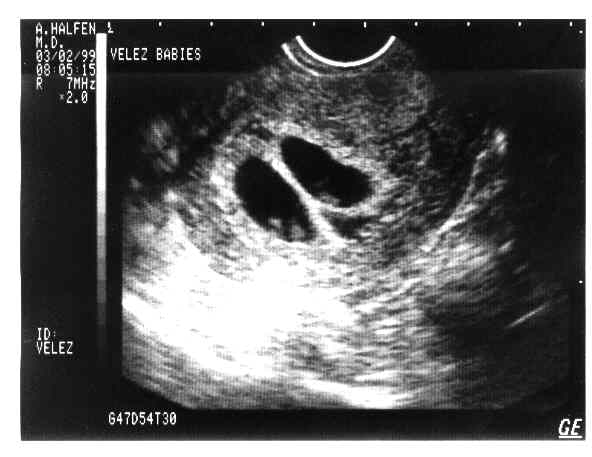

eggs2.JPG - 19.8 K eggs3.JPG - 22.4 K eggs4.JPG - 11.7 K babies-1a.JPG - 21.3 K